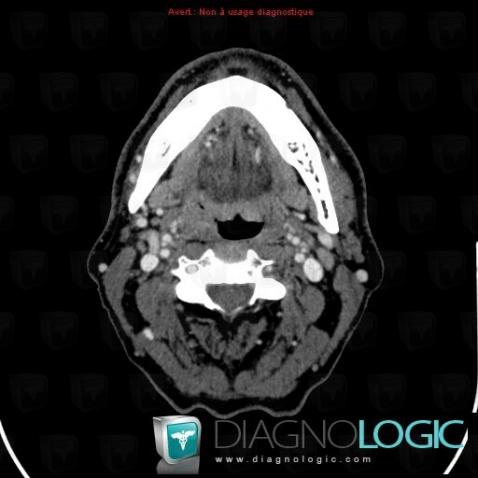

Pharyngeal carcinoma, Pharyngolarynx, CT

Here is the specific information in the key image above:

- Diagnosis Pharyngeal carcinoma, Location(s) Pharyngolarynx, with gamuts Piriform sinus mass